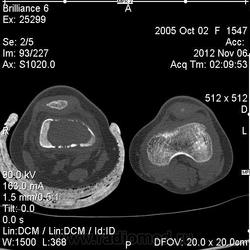

Девочка 8 лет. Обратилась за помощью в связи с травмой - ударилась коленом, почувствовала боль. Ранее ничего не беспокоило. Выполнены рентгенограммы, затем КТ.

1. ГКО или аневризмальная киста в активной фазе? Смущает агрессивность процесса - массивный лизис, местами какая-то даже изъеденность кости, выражена реакция мягких тканей вокруг очага.

2. Злокачественный процесс? Но опять полностью без предшествующей клиники?

Исправила комментарий. Не ГКО. Возраст, диафиз, центральное. Контуры четкие. Немного вздута кость. Киста либо эозинофильная гранулема. Всё равно без биопсии некуда.

В диф.ряд поставила бы ГКО, аневризмальную кисту в активной фазе, но нельзя исключить и зло, учитывая изменения кортекса, хоть и нет периостоза. Недавно был ребенок тоже с большим литическим очагом в метафизе большеберцовой кости, небольшим вздутием и совершенно без периостоза (правда, на фоне какой-то дисплазии), оказалось остеогенной саркомой.

На боковой рентгеннограмме, по задниму контуру определяется прерывистость кортикального слоя - это мне мерещиться, или же это симптом "козырька" и есть? (который встречается при злокачественных опухолях костей)

Результаты исследования материала гистологами в Москве: аневризмальная киста.